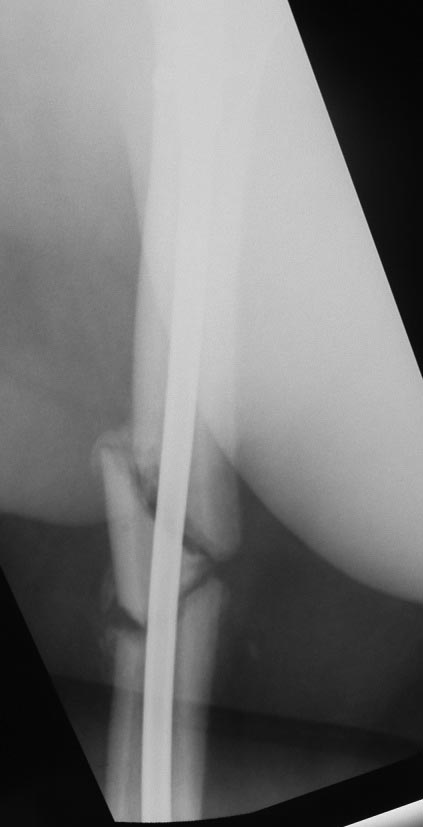

Уважаемые коллеги. Хотелось бы выслушать мнения и советы по представленному случаю. Пациент 42 лет, вес 130 кг, рост около 160 см, сахарный диабет в легкой форме (впервые выявлен после травмы). Травма в феврале 2011 г. - упал с мотоцикла на отдыхе за рубежом. По возвращении в Россию был прооперирован в несколько этапов: в марте 2011 г. - остеосинтез обеих костей правого предплечья пластинами по поводу открытого перелома; интрамедуллярный остеосинтез правого бедра; остеосинтез проксимального конца правой большеберцовой кости. В апреле 2011 г. был доставлен 1 блокирующий винт в дистальное отверстие гвоздя и выполнена пластика крестообразных и наружной боковой связок левого коленного сустава. В феврале 2012 г. были удалены фиксаторы с проксимального конца правой большеберцовой кости и выполнена пластика крестообразных и наружной боковой связок правого коленного сустава. За это время пациент смог начать ходить, сначала с костылями, а затем - без дополнительной опоры. Летом 2013 г. решил укрепить ноги с помощью подъемов пешком на пятый этаж. В результате - усталостная рефрактура правого бедра и перелом интрамедуллярного гвоздя. 09.09.2013 - реостеосинтез латеральным бедренным гвоздем с пластикой костной аутостружкой + СhronoS. Сейчас, через 6 мес после операции, может ходить без дополнительной опоры, периодически беспокоит болезненность в области правого бедра. На сегодняшних КТ - отсутствие признаков консолидации. Нужно ли что то делать и, если да, то что? Рассматриваемые варианты: повторная костная пластика дефекта; доставить блокирующие винты (самый проксимальный винт был удален через 3 мес после операции). Еще раз менять гвоздь не хотелось бы. На представленных снимках: бедро в 2011 г., через несколько мес после операции; в 2012 г., на стадии консолидации; со сломанным гвоздем; сразу после повторной операции (3 рентгенограммы). Все КТ - сегодняшние. Заранее спасибо за ответы.

А какой диаметр последнего стержня? По представленным снимкам кажется, что тонковат...?

Второй гвоздь был на 2 см длиннее и на 1 номер толще предыдущего. По-моему десятка.В принципе какая разница? Впечатление о том, что тонковат, ведь не зависит от реальной толщины гвоздя. Канал не рассверливал. Но забивал с трудом.

Мне тоже показалось, что тонковат. Но, раз операция нежелательна, надо ждать и лечить консервативно. При неуспехе - на мой взгляд, замена стержня на более толстый с рассверливанием канала и, возможно, костной пластикой.

ждать-не ждать? Срочности нет, подождать можно, но активно, т.е. оценить клиническую и рентгенологическую динамику: два месяца назад, сейчас и еще через пару месяцев. Уменьшатся боли, появится более убедительная мозоль - ждите и наблюдайте дальше. Отсутствие положительной динамики можно приравнять к отрицательной динамике. Очевидно, что здесь имеют место быть обе проблемы: биологическая -мозоль слабая и механическая - тонкий гвоздь, недостаточная стабильность. Тогда -удаление, рассверливание (очень аккуратное, по 0.5 мм шаг, острыми фрезами, чтобы не пожечь кость - кортикал толстый и довольно прочный). Для 130 кг диаметр гвоздя минимум 12 мм, лучше больше. Здесь можно и 14мм гвоздь взять и блокировать дистально винтами 6,0 мм. Открывать перелом и пытаться делать еще пластику экстрамедуллярно не стоит. Рассверливания будет достаточно.

Согласен, стержень тонковат в дистальном отломке. Если совсем никак не возможно перепровести с рассверливанием более толстый стержень, можно согласиться с вашим предложением ввести еще один винт в дистальный конец гвоздя, но полностью убрать винты из проксимального отломка, чтобы перенести осевую нагрузку на кость и не опасаться перелома гвоздя или винтов.

Насколько это эффективно в отношении консолидации будет видно примерно через 6 недель. Незабудьте сделать, если его нет, обычный свежий снимок до динамизации для последующего сравнения.

Источник проблем - отсуствие рассверливания, тонкий гвоздь и костная пластика. При интрамедуллярном остеосинтезе (относительная стабильность) класть кусочки кости открыто бесполезно - не приживут. Только еще ухудшили кровоснабжение концов. А что там с длиной сегмента? Если длина не потерялась - реостеосинтез с рассверливанием, как А.Семенистый написал. Если укорочение - удалить, остеотомия на другом уровне и дистракиця, на стыке - компрессия, и по достижении нужной длины - заштифтовать с рассверливанием, аппарат снять только после запирания гвоздя.

При сопутствующей травме грудной клетки или при политравме допускается фиксация тонкими гвоздями с минимальным или без рассверливания канала. Тактика уменьшает second hit при damage control и стабилизирует перелом временно, но не гарантирует сращение. Рассверливание канала, кроме стабильности, создает экзотермическую температуру, которая улучшает ангиогенез за пределы канала, и поэтому происходит образование эндооссальной консолидации.

Боли в области ложного сустава подтверждают, что ожидания не помогут и приведут к повторному перелому интрамедуллярного гвоздя. Стандартная процедура - рассверливание и толстый гвоздь в динамике. Нагрузка с первых дней.